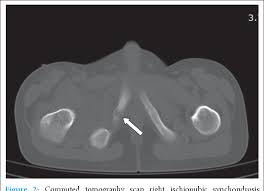

The different characteristics by images from simple radiography computed tomography MRI and bone. Van Neck-Odelberg disease is a benign process that develops in children between the ages of 4 and 16 years. Van Neck-Odelberg disease or ischiopubic osteochondritis is a rare cause of pain in the pediatric pelvis due to late closure in synchondrosis ischiopubic whose main symptom is an asymmetric pain that can cause a limitation in movement or limp.

Its radiological features may mimic stress fracture neoplasm osteomyelitis or posttraumatic osteolysis. Differential diagnosis such as stress fractures osteomyelitis tuberculosis post-traumatic osteolysis or any neoplasia is need be ruled out to arrive at diagnosis. Medical Eponyms Farlex 2012.

Se conoce entonces como síndrome de Van Neck-Odelberg a la osteocondritis isquiopúbica que se desarrolla en niños entre los 4 y 16 años. The literature to date contains fewer. A Case of van Neck-Odelberg Disease and Intermittent Overuse Injury Abstract. Van Neck-Odelberg disease is a benign process that develops in children between the ages of 4 and 16 years. Patients typically complain of vague groin or buttock pain. The different characteristics by images from simple radiography computed tomography MRI and bone. It is a temporary joint which is slimming to obliterate a bone fusion with skeletal maturation. Left leg dominant patient presented with pain in groin and limping with left leg dominance. Differential diagnosis such as stress fractures osteomyelitis tuberculosis post-traumatic osteolysis or any neoplasia is need be ruled out to arrive at diagnosis.

The synchondrosis ischiopubic SIP is the cartilaginous union between the lower ischium and pubis branch in infancy. BACKGROUND Van Neck disease VND is a benign skeletal abnormality of children involving a hyperostosis of the ischiopubic synchondrosis IPS seen on radiographs. Van Neck-Odelberg disease is a syndrome characterized by an atypical ossification pattern of the ischiopubic synchondrosis. The van Neck-Odelberg disease is hyperostosis of ischiopubic synchondrosis IPS. Der Morbus van Neck oder Morbus Odelberg-van Neck ist eine seltene Form der aseptische Knochennekrose im Bereich des Beckens Synchondrosis oder Osteochondrosis ischiopubica. In van Neck-Odelberg disease an enlarged anatomical structure called ischiopubic synchondrosis is susceptible. However the radiological findings corresponded instead to van NeckOdelberg diseasea rare benign aseptic bony necrosis of the ischiopubic.